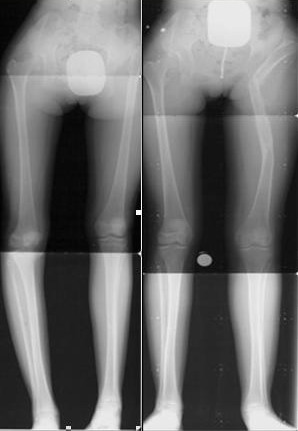

Коллеги из отделения детской ортопедии и травматологии обратились за консультацией. Девочка, 12 лет. Диагноз: врожденный вывих левого бедра с образованием неартроза, coxa valga sininstra, укорочение левой нижней конечности до 5 см, варусная деформация левого голеностопного сустава.Из анамнеза - диагноз был выставлен после рождения, получала функциональное лечение, в 1995 г. - скелетное вытяжение, потом гипс. В 96-ом разрешили осевую нагрузку в шине Виленского. Из-за неких семейных проблем перестали наблюдаться у врача. Через год - перелом н/3 левой голени, закончившийся неправильным сращением. В 1999 г. - остеотомия и АВФ. В настоящее время - соматически без особенностей, ходит самостоятельно, объем движений в тазобедренном суставе: отведение - Д 120, С 110; ротацию снаружи-внутрь - Д 40-30, С 15-20, общее укорочение конечности 5 см, в т.ч. голени - 1,5 см. 12 мая планируется консилиум. Очень хотелось бы узнать ваши мнения по поводу оперативного лечения? Заранее благодарим! С уважением, А.В.Владзимирский Донецкий НИИ травматологии и ортопедии

3.jpg

21KB (21945 bytes)